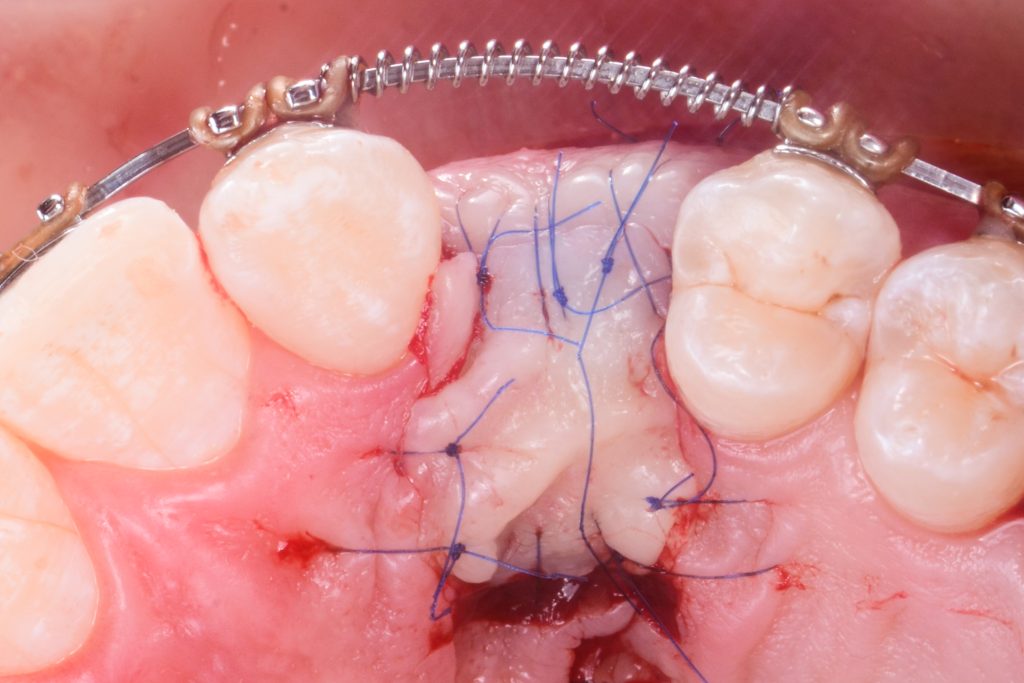

the sliding island flap secured with 6/0 stitches

the situation 10 days after the surgery